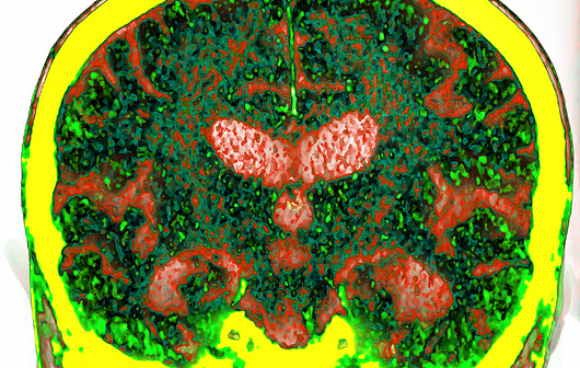

مقطع لوعاء دمويّ في الدّماغ (بالأسود)، تحوي جدرانه الخلايا البطانيّة المتكاتفة. تحيط به الخلايا الدّبقية (بالأخضر) والخلايا العصبيّة (بالأحمر). الحاجز الدّموي الدّماغيّ | المصدر: C.j.guerin, Phd, Mrc Toxicology Unit, Science photo Library